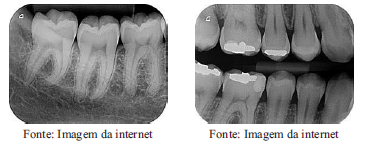

As imagens abaixo ilustram dois tipos de radiografias odontológicas. A denominação CORRETA dessas radiografia é, respectivamente:

A

interproximal e bitewing.

B

oclusal e interproximal.

C

periapical e interproximal.

D

periapical e panorâmica.

E

bitewing e oclusal.